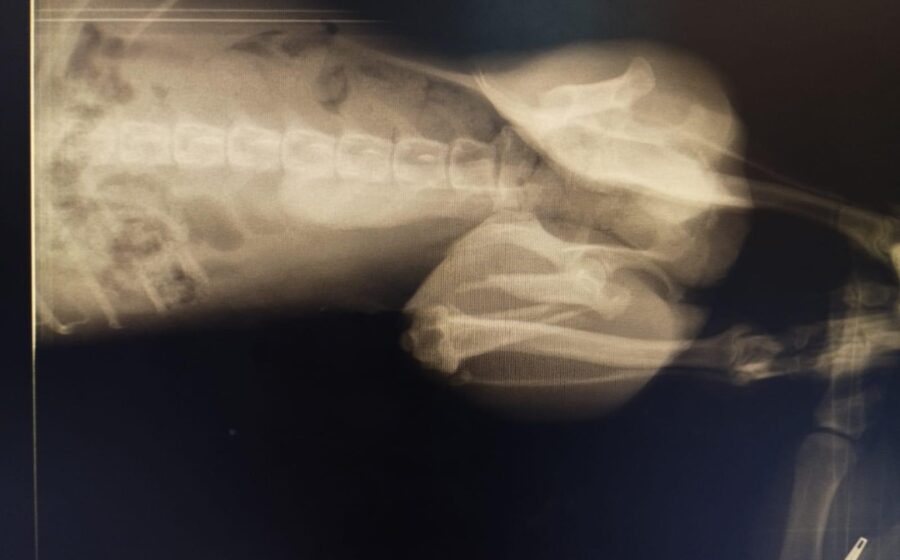

Er hat bereits eine Operation am Bein hinter sich. Doch ein neues Röntgenbild zeigt, dass leider auch seine andere Hüfte gebrochen ist. Eine zweite Operation ist daher notwendig. Danach benötigt er eine spezielle physiotherapeutische Betreuung, um wieder vollständig auf die Beine zu kommen. Er ist ein Kämpfer und hat es so sehr verdient, endlich schmerzfrei zu leben.